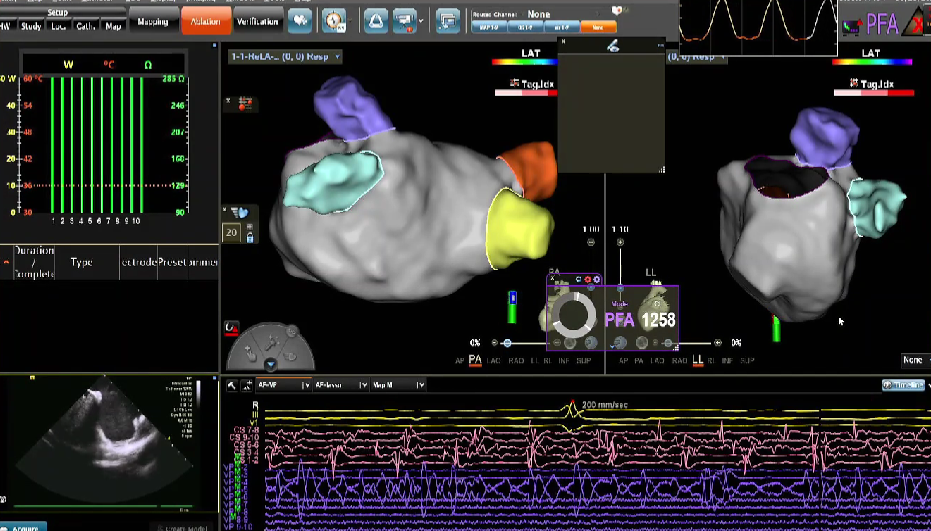

同为直播周开场致辞的中国医学科学院阜外医院姚焰教授表示:在近30年临床医学中,心律失常领域是最重大的突破学科,开创了通过微创技术基本治愈或接近治愈大部分心律失常疾病的局面。强生公司的技术和理念也在这一时期占据绝对主导地位,既造福了广大患者,也成就了众多医生。当前进入房颤治疗新时代,日本75%的导管消融手术已针对房颤患者,我国未来也将走向这一趋势。在技术层面,我们正经历从射频消融向脉冲消融的转变。根据阜外医院的日常使用经验,强生在脉冲消融产品的最大优势在于平稳过渡:沿用现有建模技术、三维标测、导航系统,仅需更换消融环状大头(即VARIPULSE导管)并增加相关线圈即可。产品学习曲线平缓,适应期短,实际效果良好。希望通过本次会议分享经验,助力各位同道更好使用该产品,共同取得优异临床成果。

VARIPULSE作为首款搭载Carto三维平台的脉冲消融产品,自上市以来,凭借其“高效”、“绿色”与“贴靠”三大核心价值,赢得了国内专家的广泛认可。上市百日内,已成功服务近七百位中国患者,实现近100%的即刻手术成功率,平均消融时间仅35分钟,且超过20%的手术在零射线条件下完成。凭借这一卓越的临床表现,VARIPULSE不仅为医疗工作者提供了更先进、更全面的治疗方案,也为广大患者带来了恢复窦性心律的新希望。

在本次电生理手术直播周期间,20位资深术者通过实时手术演示,全方位展现了 VARIPULSE脉冲消融系统在房颤治疗中的高效与绿色优势,将其临床性能推向极致。手术数据亮眼——全场直播的平均消融时间仅28分钟,充分印证了该系统的高效性;学术交流同样热烈,超50位领域专家齐聚线上,围绕‘麻醉方案优化’‘、“术式创新选择”、”并发症预防策略”等脉冲电场消融领域的核心热点话题,展开深度研讨与观点碰撞。